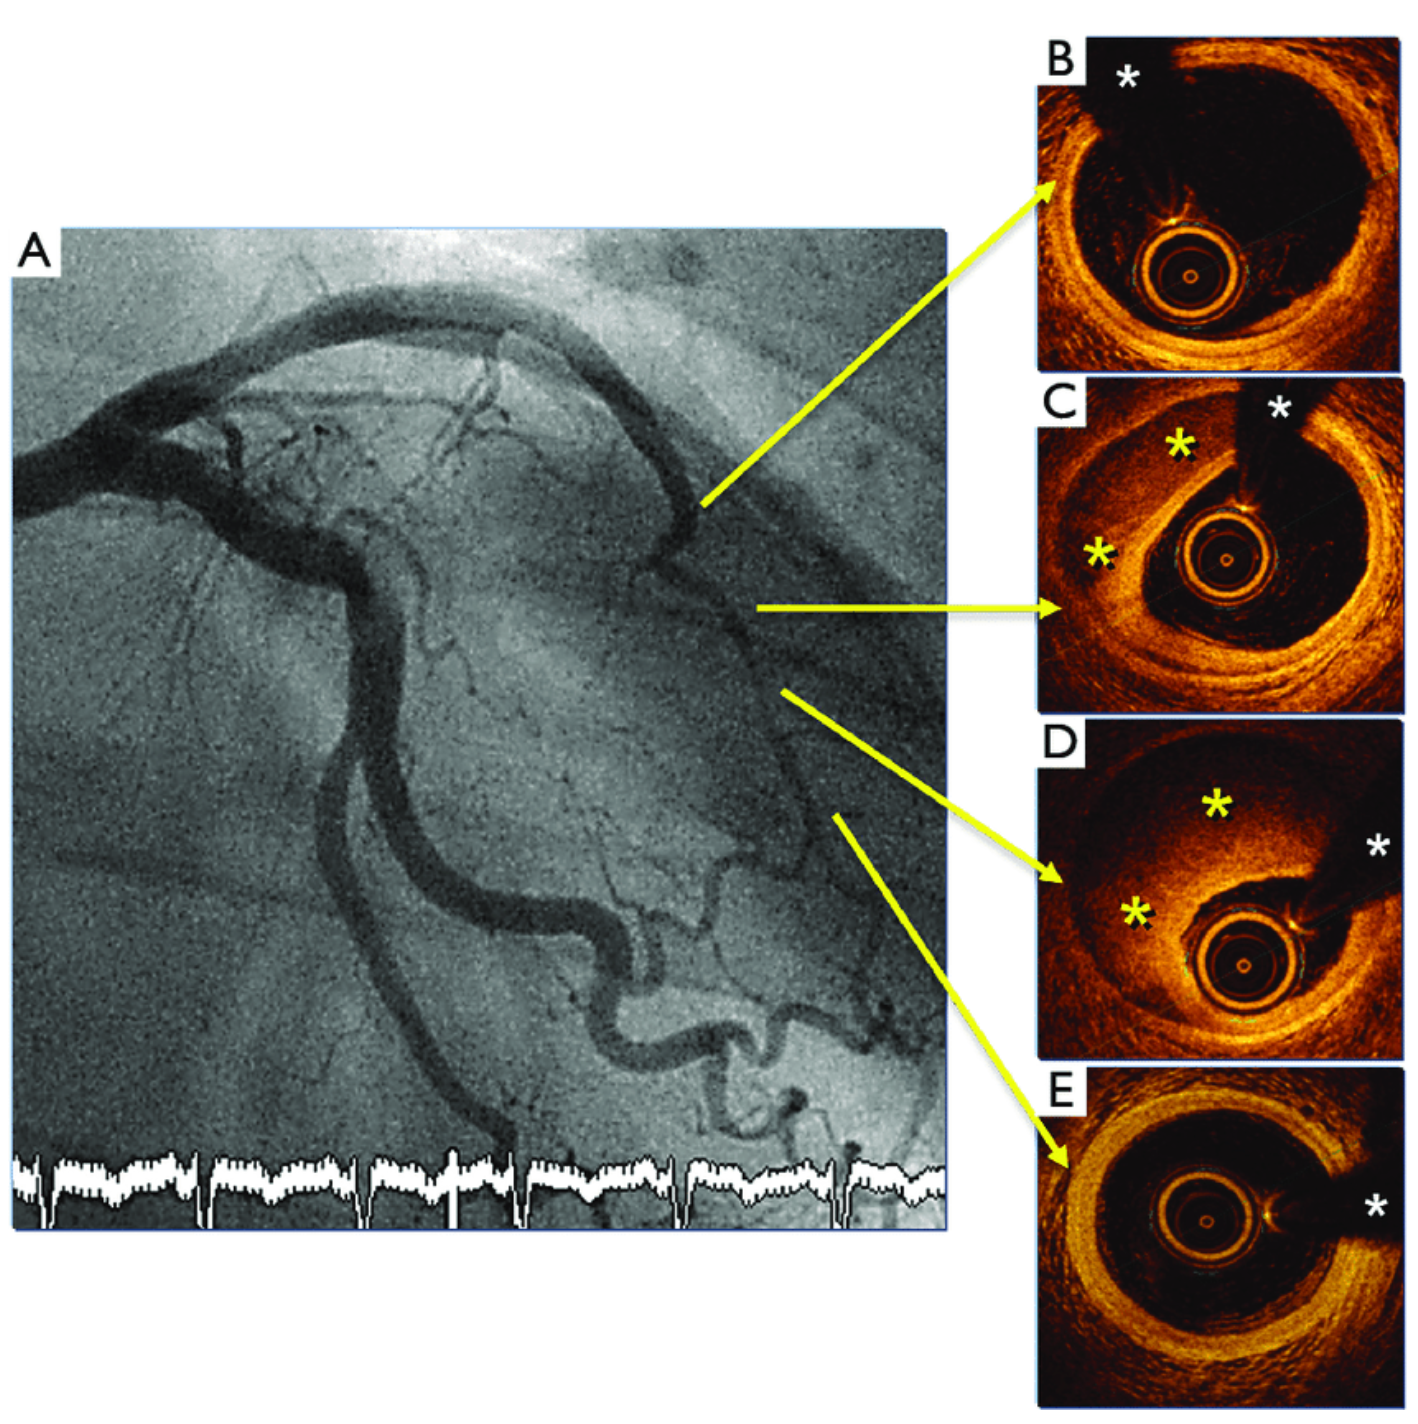

這個案例也是來自於一位有ACS症狀的患者,案例中可以見到在B處的OCT影像,可見正常的血管壁範圍。在C、D可見明顯嚴重血管腔受到intramural hematoma壓迫而產生血管狹窄。在CAG攝影下就會見到很長一段的血管突然變小。

我們的這個案例(Fig.6),也可以見到在RCA有很長一段的血管突然變狹窄。

紅色圈圈是很長一段血管突然狹窄區塊(intramural hematoma壓迫血管的地方)

黃色箭頭隱約可見原本血管壁管腔的位置